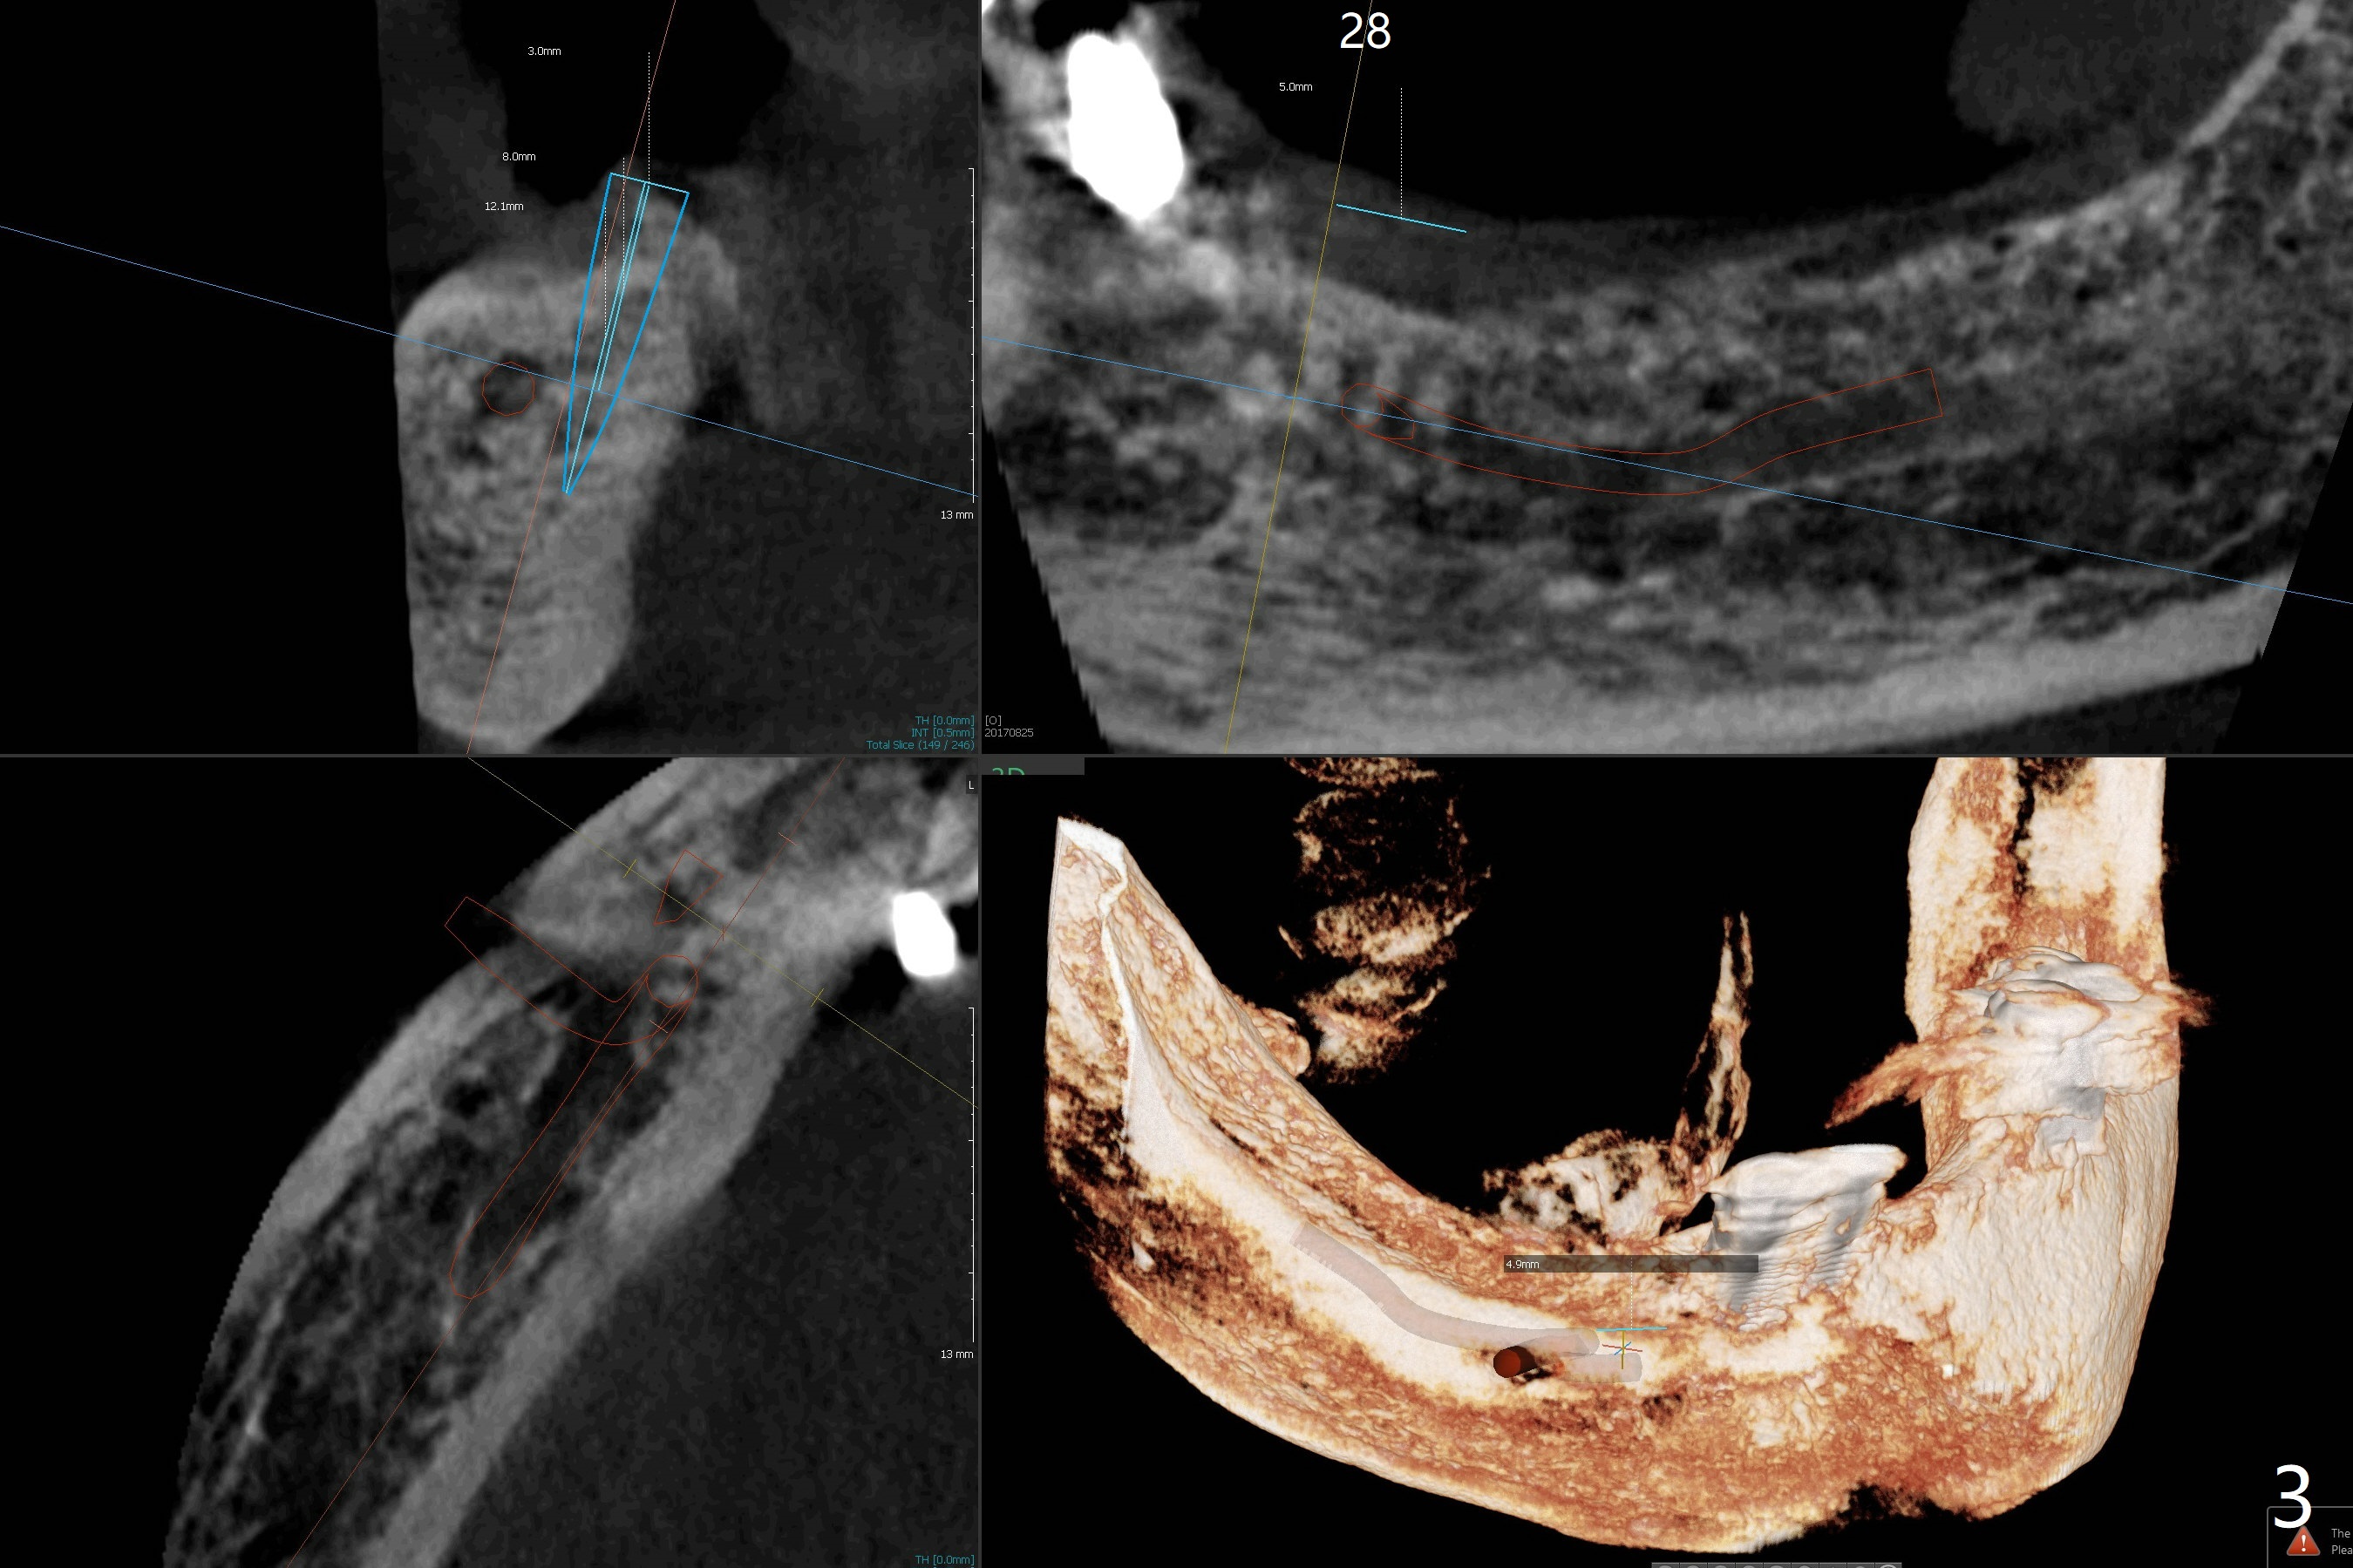

Following placement of a 3 mm 1-piece implant at #26 and two 3.8 mm 2-piece implants with ball abutments at #20 and 21 for a lower edentulous patient, another implant with ball abutment will be placed posterior (approximately at #30, Fig.1,2 (for better spread)) or anterior (approximately at #28, Fig.3,4). The implant will be placed buccal (Fig.2) or lingual (Fig.4) to the Inferior Alveolar Canal or Incisive Canal (safer). Or an implant can be placed at #27, in which there have been 2 implant failures. The last implant was removed 3 months 20 days earlier. Make an incision, study whether the site of #27 has healed with solid bone. If an implant has to be placed at #28, dissect the Mental Nerve first. When stability is low, bury the implant.